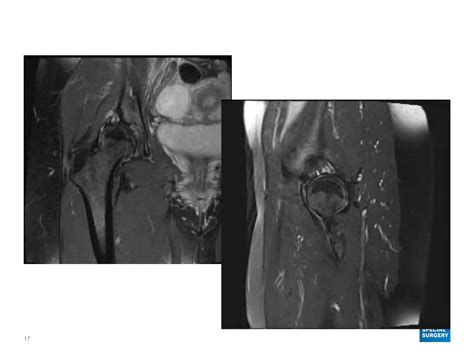

MRI Offers detailed images of soft tissues, bones, and joints, providing a comprehensive view of the cyst and surrounding structures.